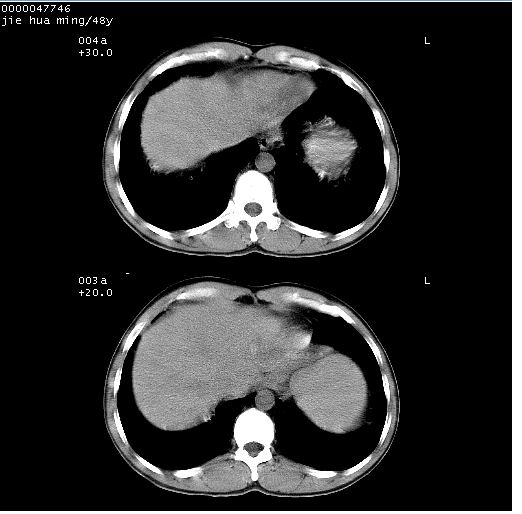

以下是引用dr.yang在2008-5-1 6:25:00的发言:[br]两肺广泛毛玻璃样的片状影,密度不均,边缘欠清,呈碎石路样改变,[br]考虑,1双肺间质性肺炎,2肺泡蛋白沉积症3支气管肺泡癌[br]

以下是引用hhcckk在2008-5-1 8:06:00的发言:[br]支持肺泡蛋白沉积症[br]依据:[br]1、病灶边缘清楚----地图征[br]2、病灶内部小叶间隔或小叶内间隔增厚所形成的网格状影----碎石路样表现[br]3、抗炎治疗无效(炎症抗炎治疗有效)[br]4、纵隔内未见肿大淋巴结(肺泡细胞癌时常有)[br][br]附肺泡蛋白沉积症资料[br][br]肺泡蛋白沉积症(pulmonary alveolar proteinosis)是一种原因不明的以肺泡腔内大量含脂糖蛋白样物质沉积为特征的疾病。[br]病理改变:(1)肺泡和细支气管腔内充满大量含脂糖蛋白样的粘稠物质,该物质为颗粒状或絮状的糖原pas染色阳性的磷脂蛋白。(2)肺泡壁及其间隔无异常改变。胸膜和淋巴结不受累及。(3)晚期可出现弥漫性肺间质纤维化。[br]临床表现:(1)好发年龄30~50岁,男性多于女性,偶见于儿童;(2)主要症状为呼吸困难、咳嗽、低热、消瘦、低氧血症和杵状指等。1/3的患者无症状。(3)实验室检查:痰液或肺泡灌洗液中可找到pas染色阳性颗粒物质。[br]hrct表现:肺泡蛋白沉积症具有特征性改变,即“碎石路样”表现(crazy-paving appearance,cpa)。主要包括(1)斑片状磨玻璃影:指肺野密度朦胧增加,内可见肺血管纹理影,系肺泡腔内充满低密度的磷脂蛋白物质所致。(2)其内部小叶间隔或小叶内间隔增厚所形成的网格状影,为小叶间隔水肿、肺泡壁内淋巴细胞和巨噬细胞浸润以及小叶内淋巴管扩张的缘故。(3)病灶边缘清楚,呈地图样分布于肺野外围或肺门及中央区。[br]

以下是引用zsl6918在2008-5-1 7:35:00的发言:[br]双肺磨玻璃样病变,可见铺碎路石征,病变区与正常区交错。边界清晰。符合肺泡蛋白质沉着征,高分辨扫描会更清楚漂亮。建议临床肺泡灌洗。

以下是引用yangyudong333在2008-5-1 5:36:00的发言:[br][br] 两肺广泛毛玻璃样的片状影,密度不均,边缘欠清,呈碎石路样改变,[br]考虑,1双肺间质性肺炎,2肺泡蛋白沉积症[br]